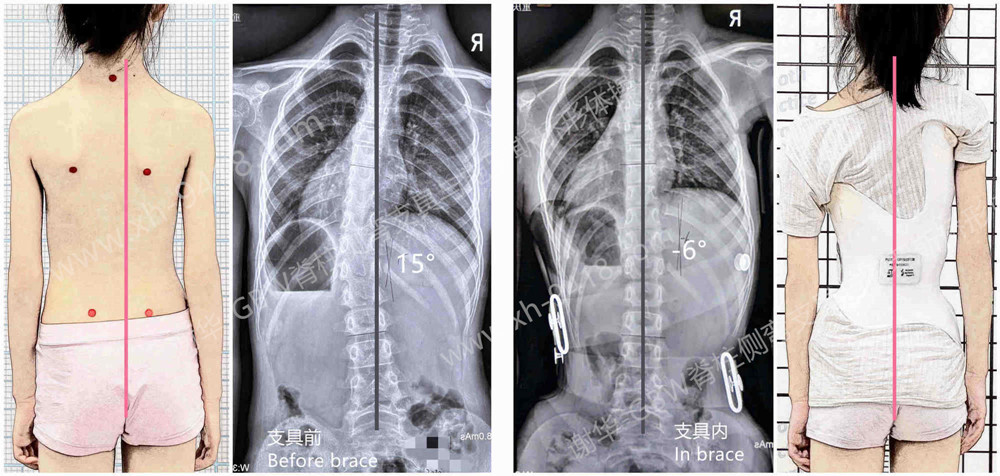

刘某,女,9岁。弯型属于一种比较少见的胸段向左侧凸曲线。经过一年的矫正后,弯度已经降至Cobb角15度,胸弯剃刀背的ATR角度也控制在6度。

不过,由于孩子目前骨龄为Risser 0级,还没有进入快速生长期,虽然弯度减轻了,但身体仍明显偏离中线,未来侧弯加重的风险依旧很高。因此,家长决定继续配置新的GBW型支具来巩固和强化矫正效果。

支具佩戴前后情况

这种类型的弯曲,在施罗斯体系中被归类为3CH左弯型。按照施罗斯矫形的原理,孩子配制了一副新的GBW支具。佩戴支具的效果比较理想——X光片显示,佩戴支具后脊柱基本回到了身体的中线上,胸弯被矫正到了-6度,出现了轻度过矫,有助于在未来的成长过程中获得更好的长期改善,减少后期进展的风险。